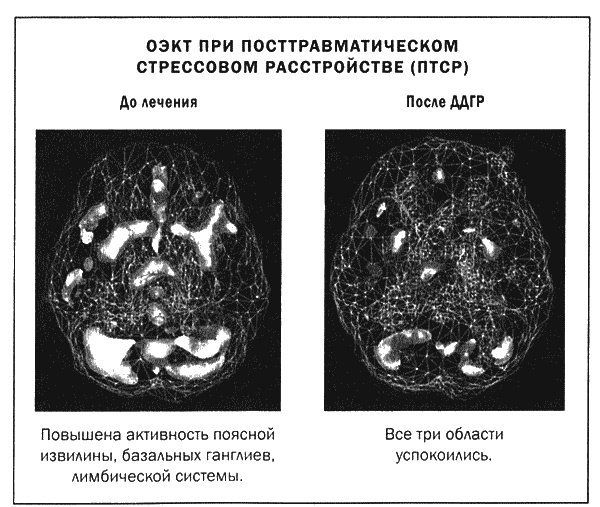

Мы проводим терапию ДДГР в Amen Clinics последние пять лет. Ею руководит психолог Дженнифер Лендл, сертифицированный тренер ДДГР, и я вижу, что эта методика очень помогает при лечении тревожности, ПТСР и для улучшения личностной эффективности пациентов. Мы изучали ДДГР с помощью методов ОЭКТ до, во время и после лечения. ДДГР действительно меняет функции мозга, поскольку успокаивает гиперактивные участки. Например, при ПТСР характерен рисунок активности мозга, который мы называем «алмазная грань»: чрезмерная активность в поясной извилине (верхняя грань алмаза), базальных ганглиях (боковые грани алмаза) и лимбической системе, таламусе (нижние грани алмаза). При таком рисунке активности мозга люди страдают от ночных кошмаров, пугливости, тревожности, беспокойства и видят мир через черные очки. Терапия ДДГР успокаивает все «грани алмаза», что доказано сканами ОЭКТ. Вот два случая из нашей практики.

Лесли было 23 года, когда она пришла на прием. В прошлом она дважды пережила изнасилования — в возрасте 15 и 22 лет, череду неуспешных любовных взаимоотношений и раннюю смерть матери (в свои 13 лет). Ее симптомами были кошмары, тревожность, депрессия и беспокойство. Скан показал типичный рисунок «алмазная грань». За четыре сессии ДДГР Лесли почувствовала себя значительно лучше. При повторной томографии выяснилось, что активность в базальных ганглиях, поясной извилине и лимбической системе снизилась.

Кейти, 32 лет, попала в дорожную аварию: грузовик выскочил на встречную полосу и снес ее автомобиль на обочину. Несколько недель она не могла нормально заснуть или снова сесть за руль. Она много плакала и часто вспоминала происшествие во всех подробностях. До этого эмоциональных травм не было. ОЭКТ показала гиперактивность по типу «алмазных граней». За три сессии ДДГР Кейти стало лучше: восстановился сон, она снова начала водить машину. Повторный скан показал снижение активности проблемных участков мозга.